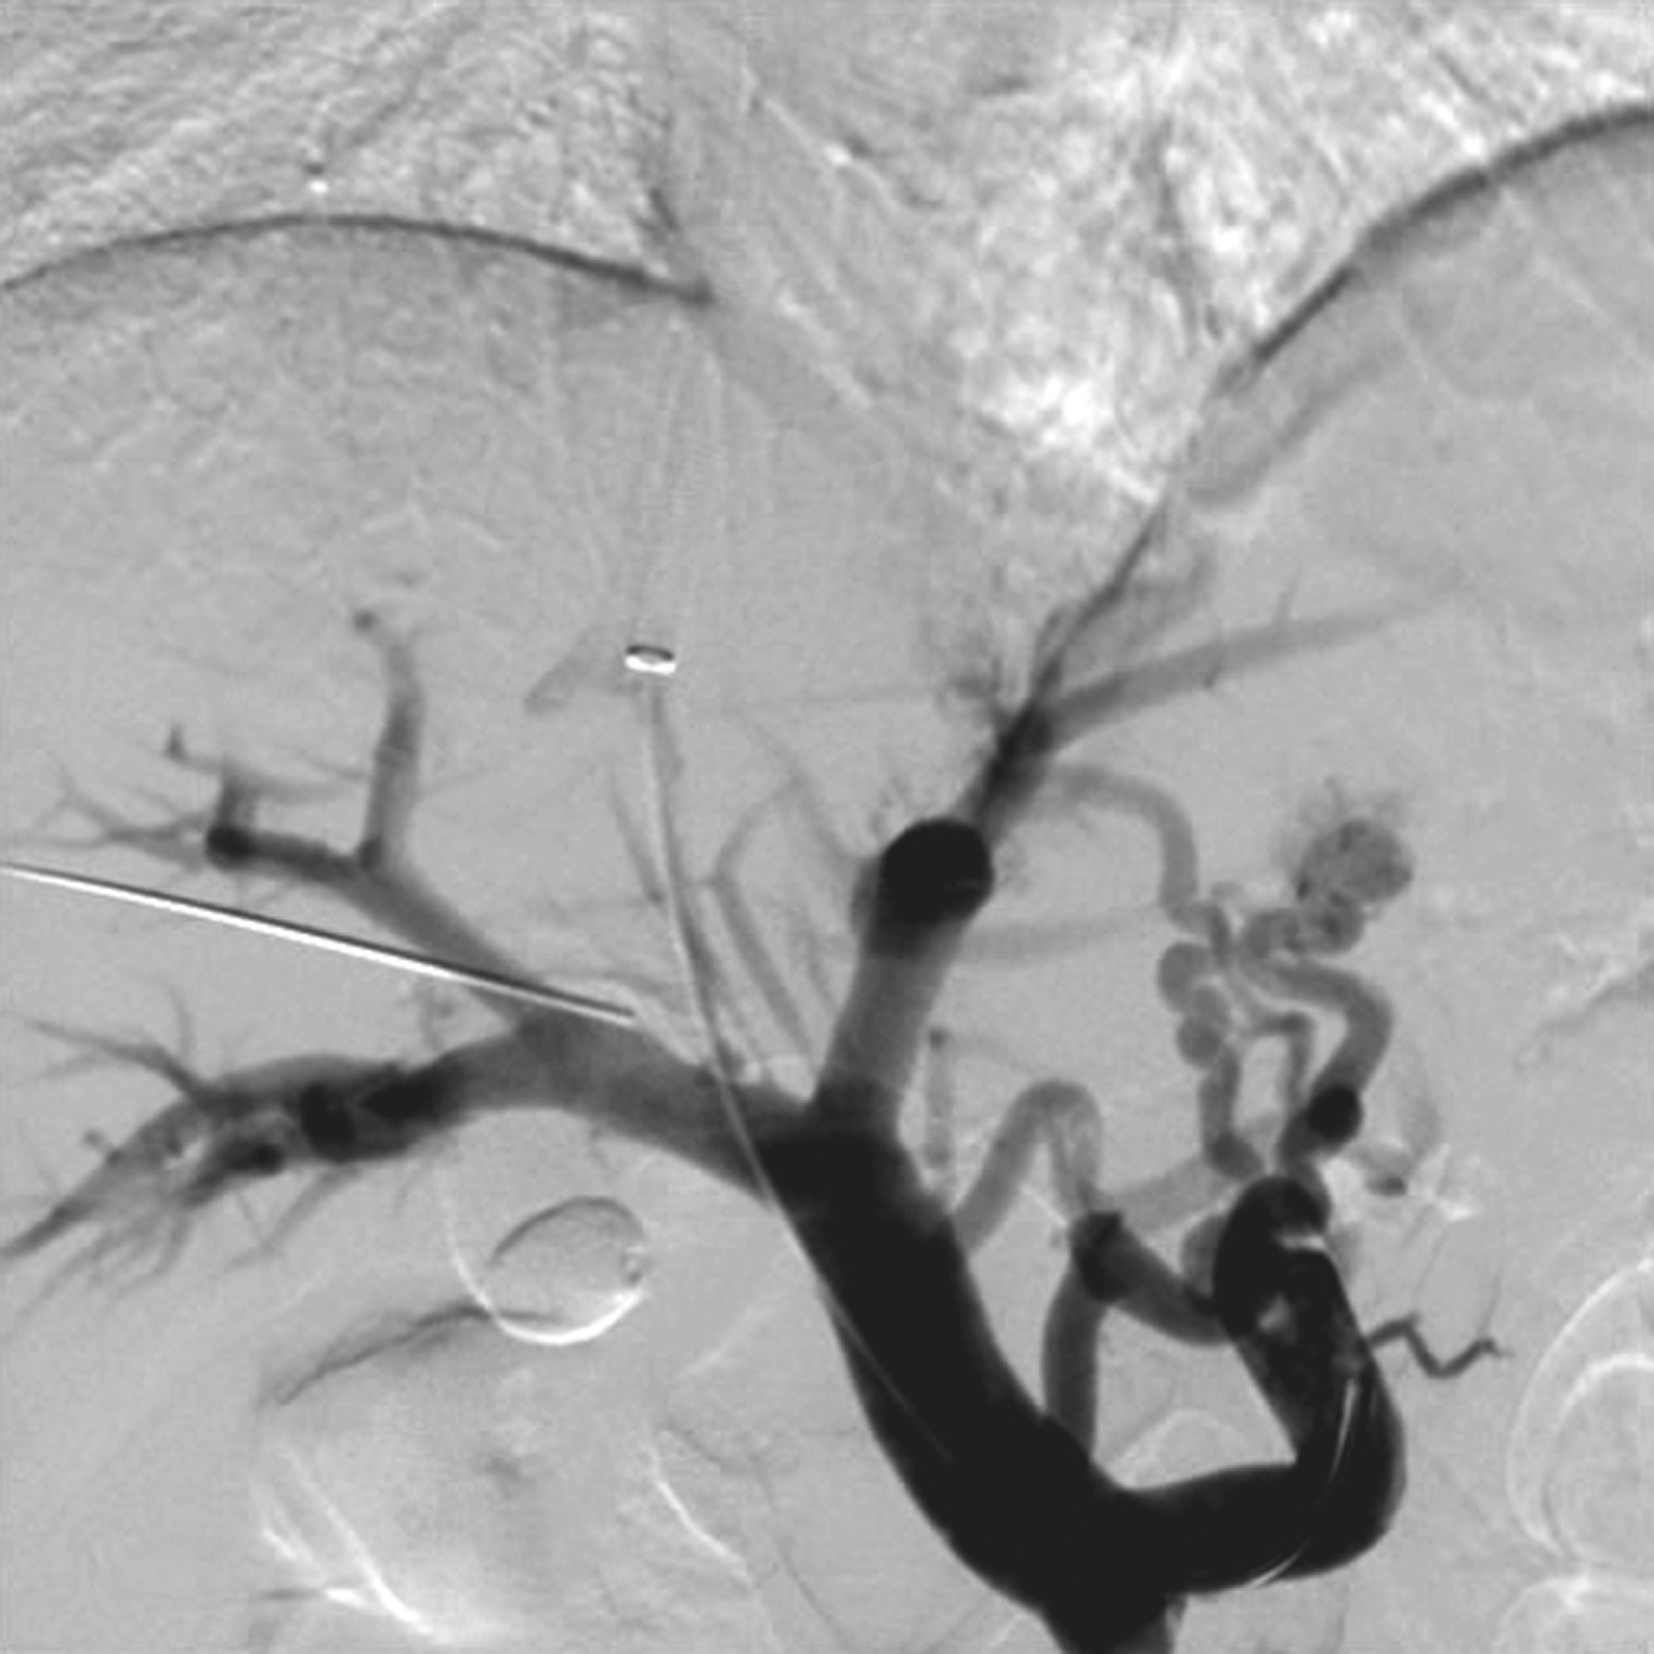

图5-21-31 继发性BCS:左肝静脉、下腔静脉及右心房癌栓致肝静脉、下腔静脉阻塞

先天性肝血管畸形较为罕见,其导致通过肝脏血流的异常分流。分三种类型:肝动静脉间(肝动脉至肝静脉)分流,肝动脉-门静脉间(肝动脉至门静脉)分流,门静脉-肝静脉间(门静脉至肝静脉)分流。胎儿发育过程中血管形成的改变导致畸形,可以是孤立性的病灶,也可是系统性疾病的一部分。如遗传性出血性毛细血管扩张症三种类型可同时存在。临床表现根据分流的类型和程度而不同。

孤立性先天性肝血管异常分流可再分为高流量分流,如动静脉畸形(arteriovenous malformations,AVM)和低流量分流(门静脉体静脉分流,淋巴管畸形)。

(1)先天性肝动静脉畸形(congenital hepatic arteriovenous malformations,HAVM):

一种先天血管畸形,分流的血液直接从肝动脉进入肝静脉,造成回心血量增加,异常血管之间无肿瘤组织。肝动静脉瘘通常发生在肝脏的某一叶段,多数患者临床症状不明显,多因体检偶然发现;分流量大者可发生高输出性心力衰竭、肺动脉高压、肝肿大、全身水肿、消耗性凝血病、贫血、门静脉高压等,死亡率达50%~90%。

【声像图表现】

肝实质回声减少代之以巢状扭曲增粗扩张的血管,病变处动脉血流流速下降,血流阻力指数减低;而静脉流速增高,频谱呈搏动性。超声可进行产前诊断,在胎儿肝脏中探及多个增大扭曲的血管。

(2)先天性肝动脉门静脉畸形(congenital hepatic arterioportal malformations,HAPM):

一种先天血管畸形,分流的血液直接从肝动脉进入门静脉,导致门静脉高压,发病罕见,在婴儿期和幼童时期所致的门静脉高压是可治疗的。先天性HAPM分为三种类型:①单支型(动脉血供为右肝动脉、左肝动脉或肝脏中动脉之一);②双支型(动脉血供为右肝动脉、左肝动脉或肝脏其他动脉分支中的两支);③复合型(动脉血供除肝动脉外还可有其他动脉,如胃动脉等,所形成的动脉血管丛)。临床表现为婴儿期和儿童期反复严重的上消化道出血,进行性肝脏杂音和脾肿大,也可产生腹水。单分支型约占总病例的50%,平均发病年龄约3岁(1周岁~16岁),单支型发病明显晚于双支型及复合型。

灰阶超声为肝动脉增粗,病变处节段性门静脉扩张,门静脉内测及搏动性血流,瘘口周围的肝实质可出现彩色斑点(振动伪像)。